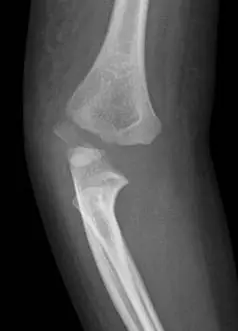

本題影像與上題相同,為治療前的診斷影像:

側面(Lateral)影像: 外髁骨折碎片向後外側移位,關節面連續性中斷。後脂肪墊徵象(posterior fat pad sign)陽性,確認關節內積血。此類 Jakob Type III 骨折的碎片旋轉特性使閉合復位困難,通常須直視下開放復位才能確保關節面解剖重建。